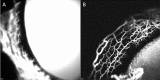

Purpose: To validate the use of aqueous angiography (AA) in characterizing distal aqueous outflow pathways in normal and glaucomatous cats.

Methods: Ex vivo AA and optical coherence tomography (OCT) were performed in nine adult cat eyes (5 feline congenital glaucoma [FCG] and 4 normal), following intracameral infusion of 2.5% fluorescein and/or 0.4% indocyanine green (ICG) at physiologic intraocular pressure (IOP). Scleral OCT line scans were acquired in areas of high- and low-angiographic signal. Tissues dissected in regions of high- and low-AA signal, were sectioned and hematoxylin and eosin (H&E)-stained or immunolabeled (IF) for vascular endothelial and perivascular cell markers. Outflow vessel numbers and locations were compared between groups by Student's t-test.

Results: AA yielded circumferential, high-quality images of distal aqueous outflow pathways in normal and FCG eyes. No AA signal or scleral lumens were appreciated in one buphthalmic FCG eye, though collapsed vascular profiles were identified on IF. The remaining eight of nine eyes all showed segmental AA signal, distinguished by differences in time of signal onset. AA signal always corresponded with lumens seen on OCT. Numbers of intrascleral vessels were not significantly different between groups, but scleral vessels were significantly more posteriorly located relative to the limbus in FCG.

Conclusions: A capacity for distal aqueous humor outflow was confirmed by AA in FCG eyes ex vivo but with significant posterior displacement of intrascleral vessels relative to the limbus in FCG compared with normal eyes.